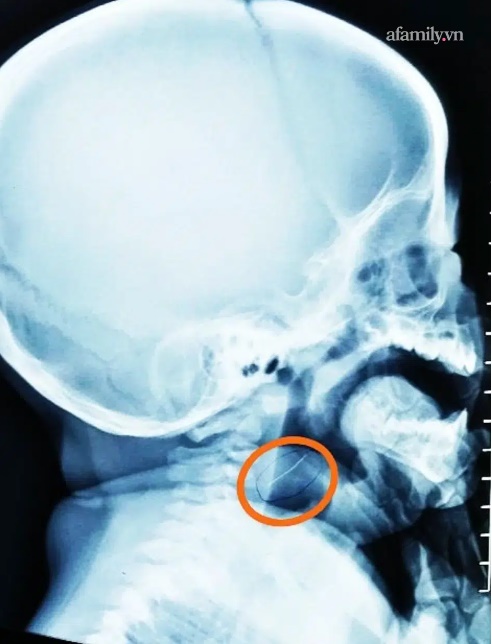

Tại bệnh viện, ngay sau khi tiếp nhận, các bác sĩ trực nhanh chóng chụp X-quang cổ nghiêng, phát hiện dị vật còn nằm ở hầu họng.

Bệnh nhi được tiến hành soi gắp dị vật khẩn và gắp ra thứ không phải là xương mà là một sợi kim loại mảnh nhưng rất cứng và nhọn 2 đầu, dài gần 2cm.

Ảnh chụp X-quang phát hiện dị vật vùng hầu họng.

Sợi kim loại này đang cắm sâu vào vùng hạ họng (sâu bằng 1/3 chiều dài dị vật), được xác định là rơi ra từ rây lưới thép, bị lẫn vào cháo trong quá trình chế biến. May mắn là dị vật chưa xuống sâu hơn nên tính mạng em bé không gặp nguy hiểm. Nếu không được gắp ra kịp thời, đoạn kim loại này có thể làm thủng đường tiêu hóa dẫn đến những hậu quả khó lường.